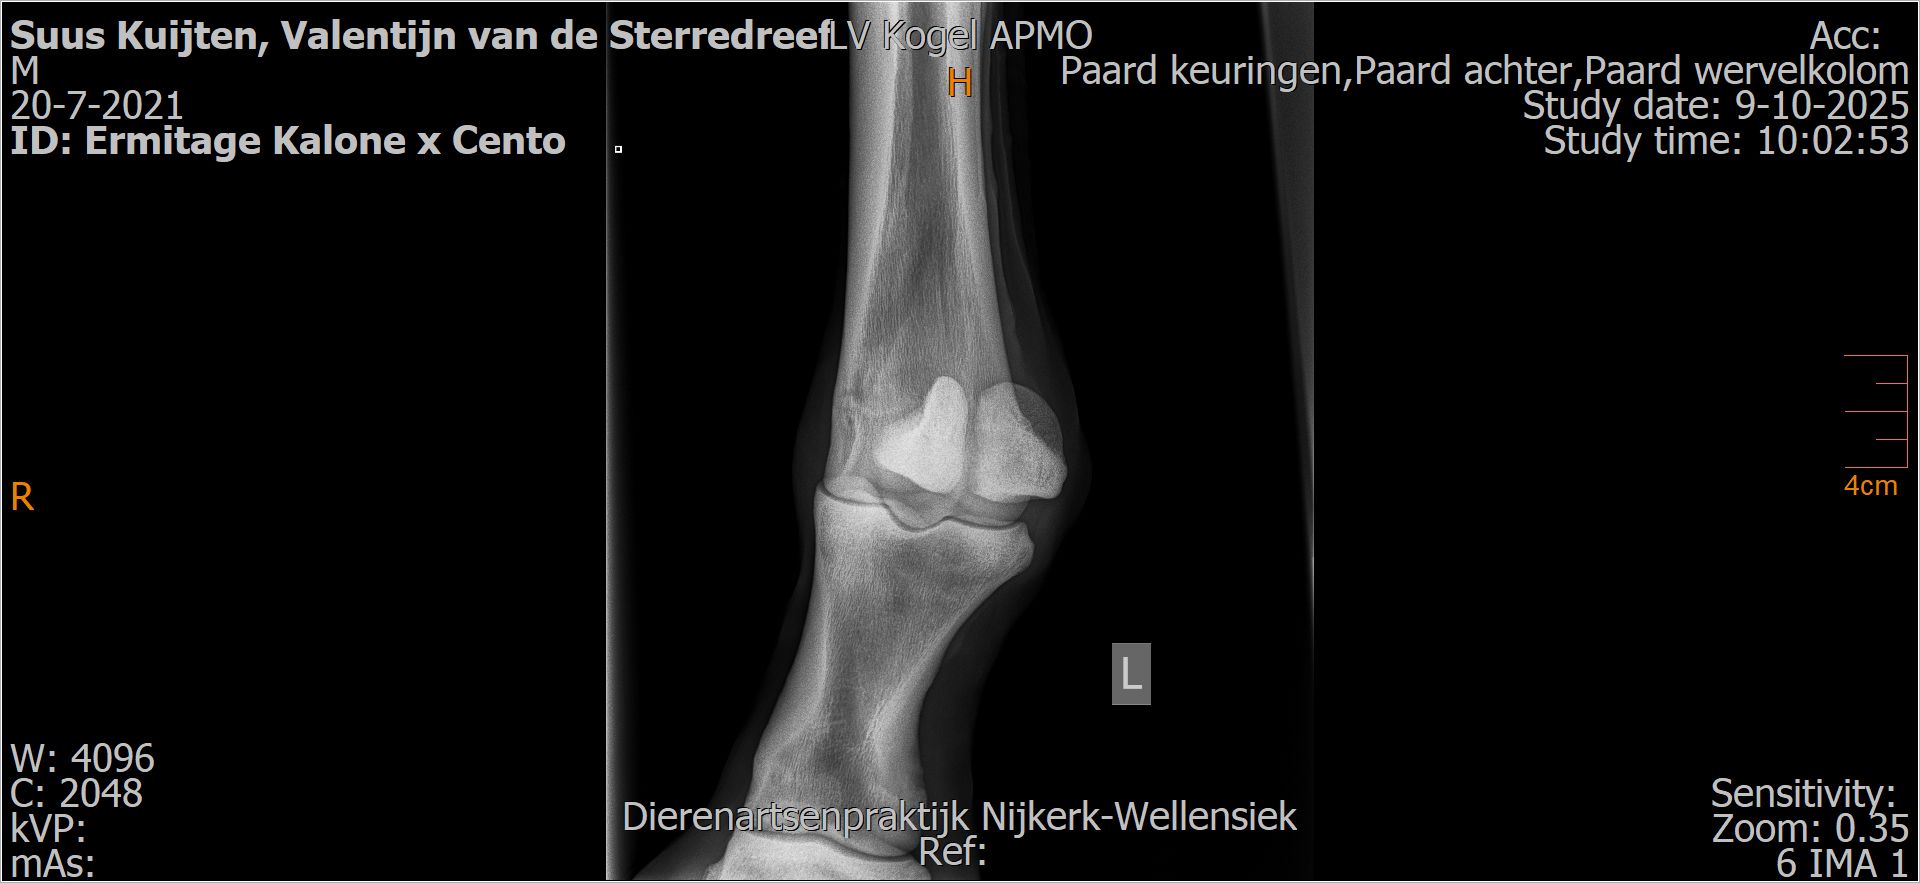

Valentijn van de Sterredreef

Röntgenfoto’s